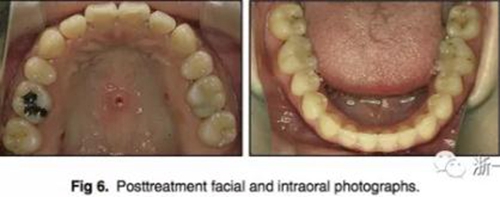

治療后全景片提示間隙得到關(guān)閉,除了左下頜第一前磨牙外牙根平行度可,無明顯骨及牙根吸收。(圖7)